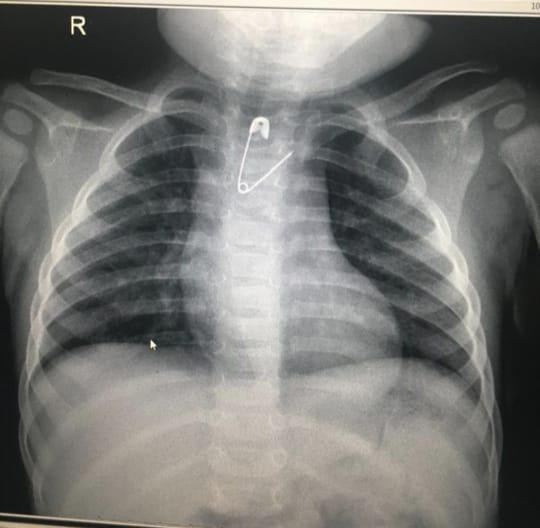

فريق طبي بولادة مكة ينجح في إزالة مشبك من مريء طفلة

تمكَّن فريق طبي بمستشفى الولادة والأطفال عضو التجمع الصحي بمكة المكرمة من إنقاذ طفلة بعمر 8 شهور بإزالة مشبك مفتوح عن طريق المناظير دون إجراء إي تدخل جراحي.

وقاد العملية الدكتور علي الشمراني وطبيب التخدير د.أنس بركات، حيث أوضح د. الشمراني قائلاً : أن مثل هذه الحالات تعد نادرة وذلك لصغر عمر الطفلة وتعتبر هذه الطفلة الأولى التي يستخرج منها هذا الجسم الغريب (المشبك) على مستوى المنطقة بعمر لم يتجاوز 8 أشهر من الجزء العلوي بالمريء, كما نوه بالتعاون البناء بين الأقسام المختلفة ومنها الأشعة والتخدير في علاج المرضى.